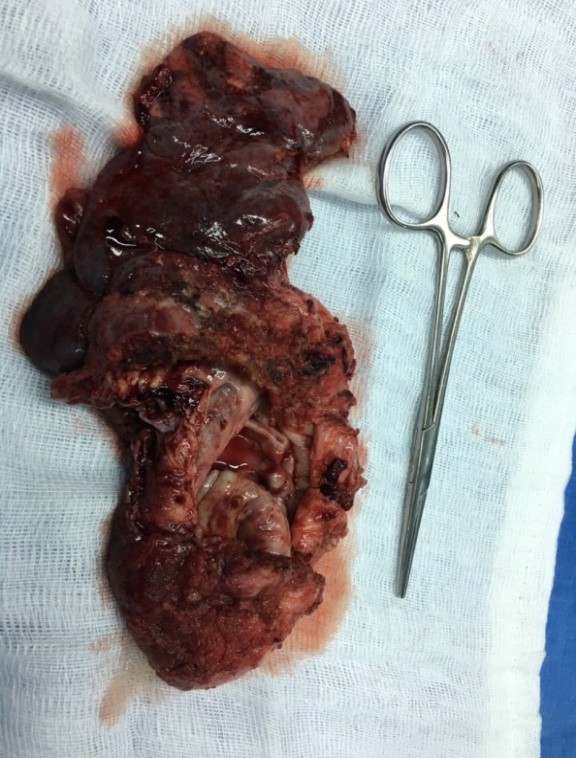

Figure 1. Chest x-ray and CT scan showing a giant bulla of the left upper lobe with compression of the remaining lung parenchyma.

A 17-year-old woman was admitted to the Thoracic Surgery Department of Da Nang Hospital in Vietnam with left chest pain, cough, and dyspnea. The medical history of this patient revealed a persistent cough for several months when she was 10 years old. Physical examination demonstrated decreased breath sounds in the left thorax. There were no other abnormal clinical findings. A routine chest x-ray and computed tomography confirmed the presence of a giant bulla of the left upper lobe (Figure 1).

The patient underwent VATS left upper lobectomy. Surgery was performed under general anesthesia with double lumen endotracheal intubation and single lung ventilation. The patient was positioned in the right lateral position. First the authors divided the lesion from the chest wall and mediastinum, which was very difficult due to adhesions between the chest wall and the left upper lobe. They then transected the branches of the upper lobe pulmonary artery. Following this, they transected the left upper lobe vein; they didn't transect the vein first because it could lead to vascular engorgement and increased bleeding. Finally, they transected the left upper lobe bronchus. After completion of the fissure, the left upper lobe was extracted (Figure 2). The total operative time was around 2 ½ hours.

After the operation, the patient was stable. A postoperative chest CT scan showed good expansion of the left lower lobe. Pathological result showed a cystic lesion of the lobe (Figure 3). The patient was discharged five days after surgery.